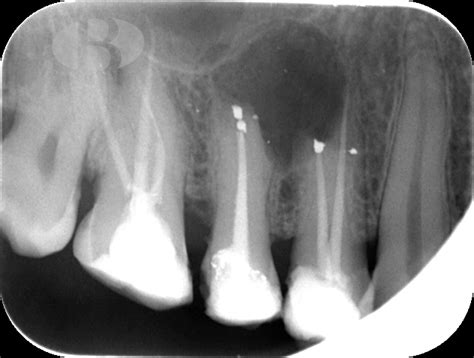

El quiste radicular se diagnostica mediante radiografías periapicales, en la radiografía los quistes se observan como una lesión radiolúcida (negras) con los bordes bien delimitados por una delgada línea blanquecina, de forma redondeada u ovalada. Sin embargo, la confirmación de la presencia de un quiste radicular se obtiene mediante imágenes radiográficas como las radiografías periapicales, las ortopantomografías (visión panorámica de ambos maxilares) o las tomografías computarizada de haz cónico (CBCT).

Durante la endodoncia, se elimina el tejido infectado de la pulpa del diente y se limpian y desinfectan los conductos radiculares. Si el origen del quiste es un proceso infeccioso, deberá realizarse la endodoncia del diente en cuestión, es decir se llevará a cabo el tratamiento de los conductos radiculares. Una vez hecha la endodoncia se tendrá que controlar. Si un paciente acude a la consulta con un tratamiento de endodoncia ya realizado, pero presenta una lesion radicular, el tratamiento que se llevará a cabo será la reendodoncia del diente afectado. Se repetirá el tratamiento de conductos siguiendo el correcto protocolo para que el tratamiento tenga éxito. Este tratamiento se realiza cuando el diente aún es viable y puede salvarse.